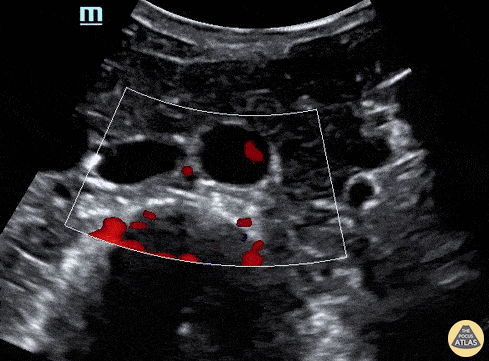

Biliary - RUQ Color Doppler

51 year old male with a chief complaint of RUQ abdominal pain for 3 days with nausea and vomiting. When looking to evaluate the aorta, IVC or gallbladder and you find multiple anechoic structures you can you use color doppler to help determine which structures have pulsatile blood flow, non-pulsatile or no flow in a effort to distinguish these anatomic structures. Lindsay Davis, DO, MPH, PGY1; @Lindsadavis18 Lydia Mansour, DO, PGY3 Emily Nagourney, MS4 Central Michigan University Emergency Medicine Residency